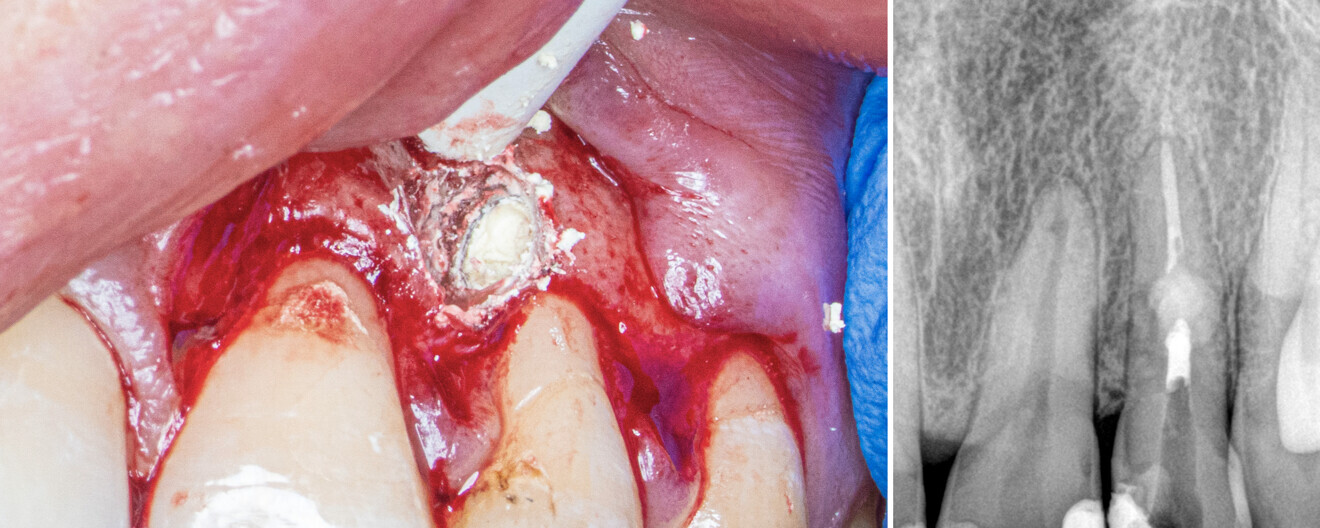

Fig. 2: Clinical situation before the treatment.

Figs. 4a & b: Biodentine filling the resorption cavity. Clinical (a) and radiographic view (b).